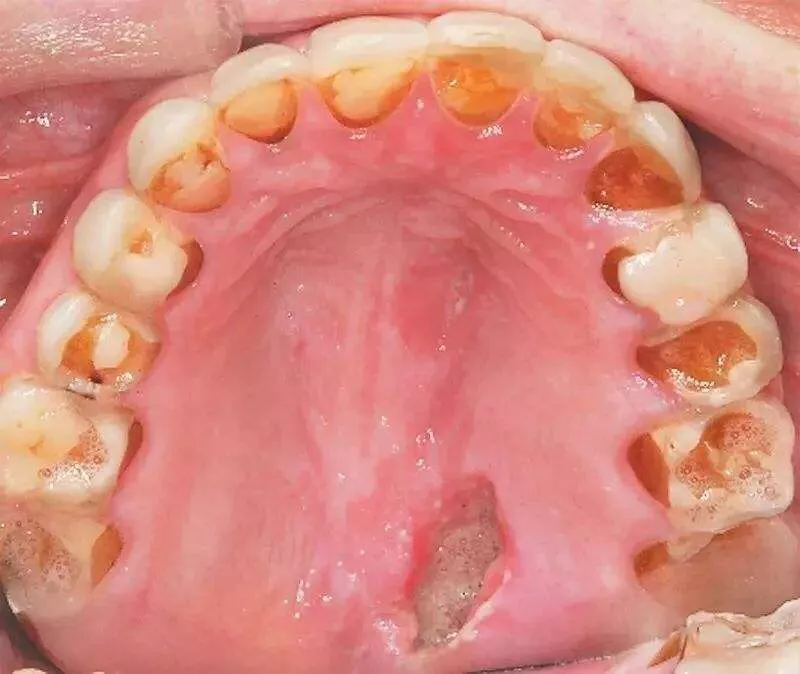

口腔溃疡各个部位代表身体哪些机能出现问题?

的溃疡性损伤病症,多见于唇内侧,舌头,舌边缘,颊,前庭沟,软腭等部位

唇内侧,以及颊黏膜等部位出现不同程度的圆形溃疡点,溃疡面有非常明显